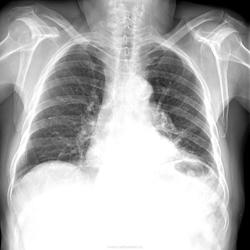

Пол пациента: Мужской пол Тип патологии: Воспалительное заболевание неинфекционной природы Область исследования: Грудная клетка и верхние дыхательные пути Методы исследования: Rg мужчина 1939 гр с направительным диагнозом пневмония? Жалобы на кашель в течении 1.5-2 месяца. Есть ли пневмония? По ФЛГ в апреле этого года -картина похожая с заключением пневмосклероз. https://radiomed.ru/sites/default/files/styles/case_slider_image/public/user/20421/2_z03.jpg?itok=l3QuH2Oc ID:39006 Ср, 18/06/2014 - 20:12 #1 Сольвейг Не на сайте Был на сайте: 3 года 10 месяцев назад Зарегистрирован: 05.02.2013 - 20:25 Публикации: 2239 В таких случаях надо левый бок делать. В данном случае-исключать "непорядок" в нижних долях (10-ках) Ср, 18/06/2014 - 20:43 #2 Татьяна Холод Не на сайте Был на сайте: 2 года 4 месяцев назад Зарегистрирован: 04.06.2014 - 22:28 Публикации: 355 Бок левый, только надо изображение перевернуть-так в программе почему-то получаетсяПриложения: Ср, 18/06/2014 - 20:46 #3 Сергей Кузьминов Не на сайте Был на сайте: 1 год 5 месяцев назад Зарегистрирован: 06.10.2012 - 15:51 Публикации: 11813 Вроде,нет пневмонии. Ср, 18/06/2014 - 20:56 #4 Сольвейг Не на сайте Был на сайте: 3 года 10 месяцев назад Зарегистрирован: 05.02.2013 - 20:25 Публикации: 2239 Не очень на левый бок похоже, но Вам лучше знать. Все равно в 10-ке. Ср, 18/06/2014 - 20:58 #5 NIL Не на сайте Был на сайте: 2 часа 29 минут назад Зарегистрирован: 25.11.2013 - 20:50 Публикации: 18217 А мне S 9 не нравится. Похоже, есть пневмония.Приложения: "Слушай всех, прислушивайся к немногим, решай сам".© Ср, 18/06/2014 - 21:24 #6 алкс Не на сайте Был на сайте: 10 лет 5 месяцев назад Зарегистрирован: 24.10.2012 - 22:55 Публикации: 2915 NIL wrote: А мне S 9 не нравится. Похоже, есть пневмония. Да и 9 и 10! Не очень-то пневмония, больше фиброз. Ср, 18/06/2014 - 21:54 #7 Mila85 Не на сайте Был на сайте: 3 года 6 месяцев назад Зарегистрирован: 15.03.2012 - 16:59 Публикации: 1790 Нет пневмонии Чт, 19/06/2014 - 17:18 #8 maker4ik Не на сайте Был на сайте: 8 лет 11 месяцев назад Зарегистрирован: 19.10.2011 - 17:49 Публикации: 2682 Mila85 wrote: Нет пневмонии + Чт, 19/06/2014 - 19:16 #9 lady.zhaneta Не на сайте Был на сайте: 1 год 6 месяцев назад Зарегистрирован: 06.07.2011 - 21:54 Публикации: 232 NIL wrote: А мне S 9 не нравится. Похоже, есть пневмония. +1

А мне S 9 не нравится. Похоже, есть пневмония.

Да и 9 и 10! Не очень-то пневмония, больше фиброз.